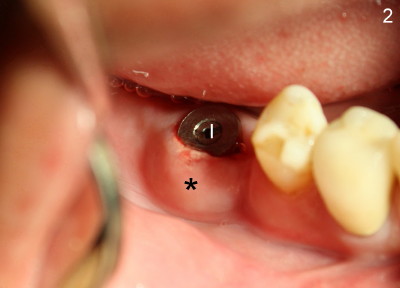

Fourteen days after placement of Tatum tapered implant (6x17 mm) in #30 edentulous area (Fig.1: I), an acute infection develops buccal to supragingivally placed implant (Fig.2: *). Why?

Postop, the patient developed both hyperthesia (pain) and paresthesia for about a week. Oral hygiene was almost abandoned due to pain. When he returned for postop infection treatment, scaling was done with irrigation of hydrogen peroxide between the implant and swollen gingiva before photography (Fig.2). In brief, when IAN injury is suspected intraop, the implant should be placed not only short of injured IAN, but also submerged to reduce contamination. The second point develops after surgery is finished. Postop, pain control and oral hygiene should be maintained.